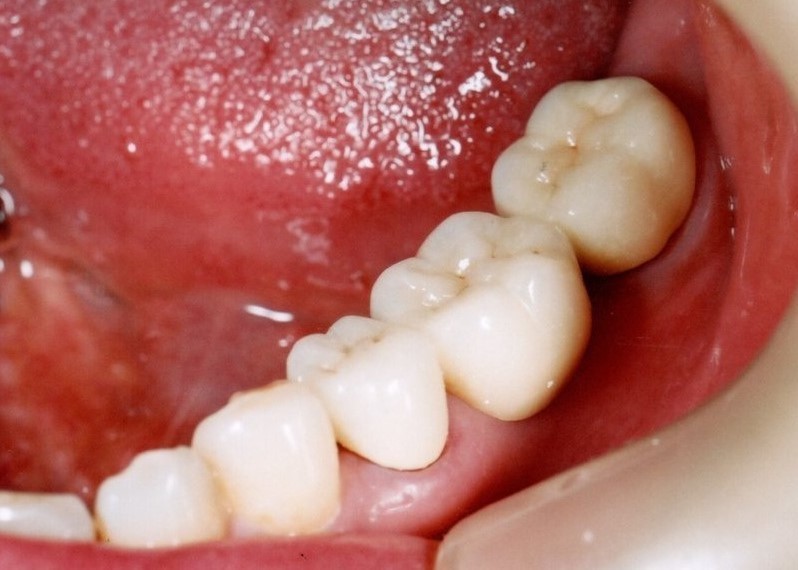

奥歯インプラント(スクリュー固定)

(伊東市 女性)

治療の流れ

むし歯で歯を失ってしまいました。

インプラントを埋入し、最終的な被せ物を装着しました。(ネジ穴をふさぐ前)

ネジ穴をふさぐとこの様な状態になります。